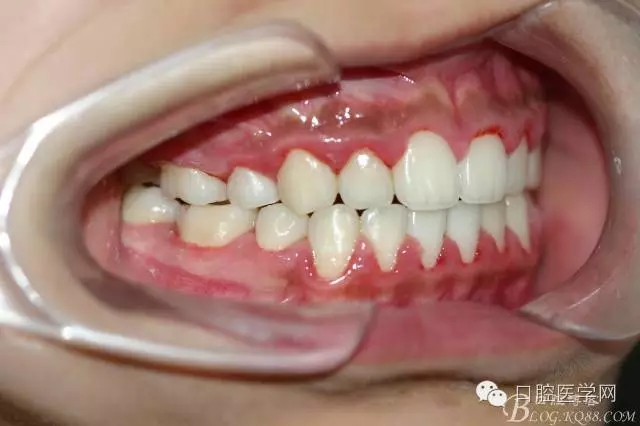

正畸查:替牙合。第一恒磨牙中性合。上牙弓尖圓型下牙弓方圓型。前牙覆合3度覆蓋7.5mm。下前牙咬到上舌側(cè)牙齦。上頜擁擠4.0mm,下頜擁擠

3.0mm。上頜稍前突下頜后縮,上下唇前突,上前牙覆蓋下唇,下唇外翻。面下三分之一過短,頦唇溝明顯,開唇露齒,頦饜窩明顯。顳下頜關(guān)節(jié)開閉口無彈響,無壓痛,開口型開口度正常。

正畸前照片: